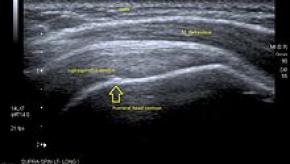

Read ArticleIs Ultrasound Changing Rheumatology Practice?

The recent inclusion of ultrasound in the classification criteria of various rheumatic diseases, such as polymyalgia rheumatica and gout, implies this imaging technique is not onlyuseful as a valued diagnostic tool for individual cases, but also on a larger scale, it will improve doctors' ability to